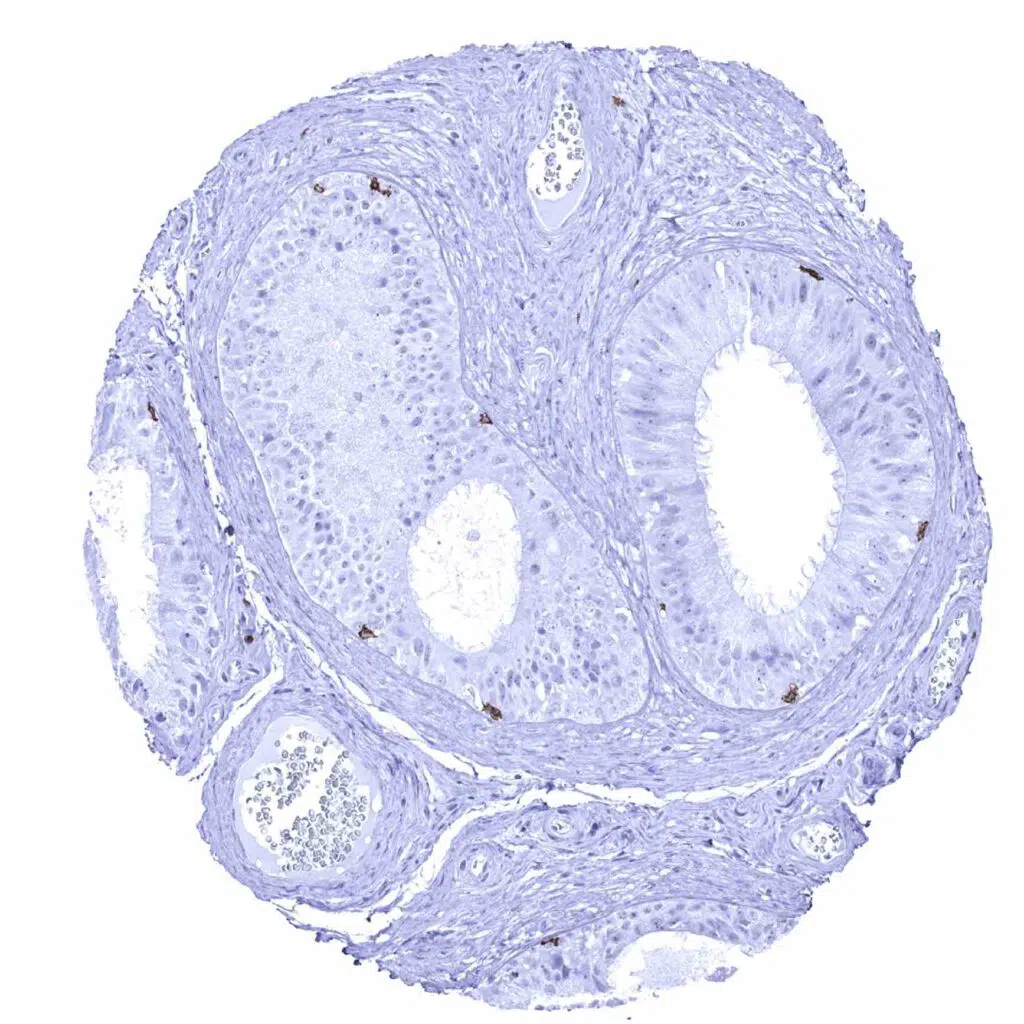

Uterus, ectocervix